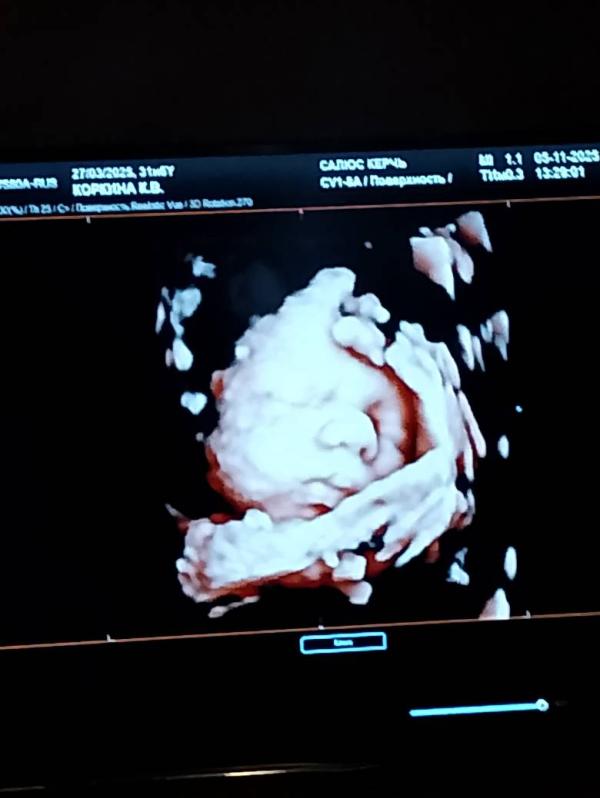

На память 🥲💕

05.11.2025

Срок 32 недели

Примерный вес 1910

Мальчишка 🥰